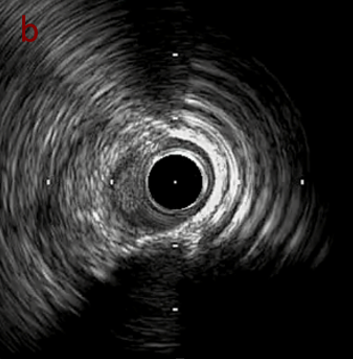

IVUS imaging

PreのIVUSではaの部位のみlipid plaqueを認め削ることでdistal embolismのリスクがあり、そのほかは270度の偏心性石灰化であるがwire biasは良好。

Pre